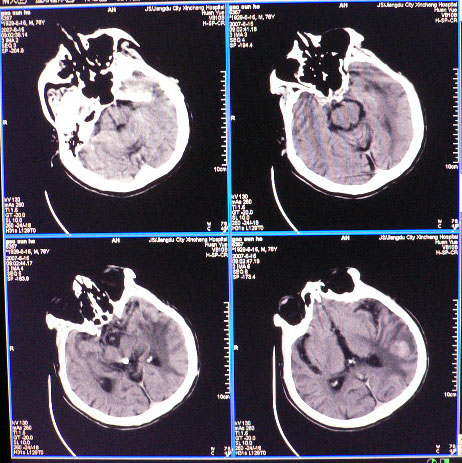

男性,78岁,失语,意识障碍1天

平扫ct值为40-45hu,增强为不均匀强化,ct值为81-85hu

皮层下厚壁花环状高密度影,明火显强化,大范围指样水肿,支持转移瘤诊断。其后上方好像还有小灶。

发生于质下,软组织影,形态不规则,周边大片水肿,明显环状强化,中间低密度液化坏死,建议结合临床